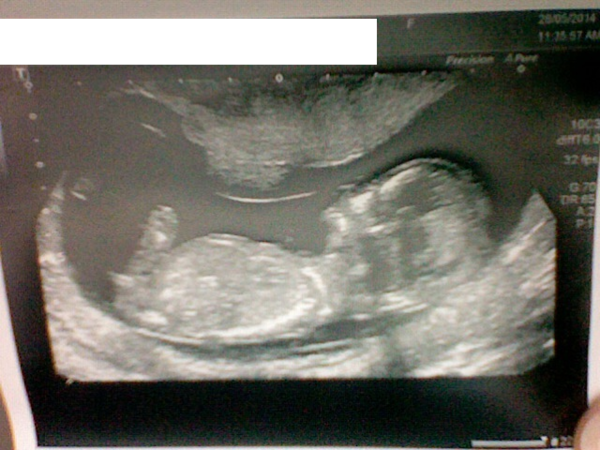

I'm just back from a anxious 12week scan (prev MMC in Oct and MC in Feb). We had the amazing news of being 14weeks and having a perfectly healthy squirmy baby. So so happy.